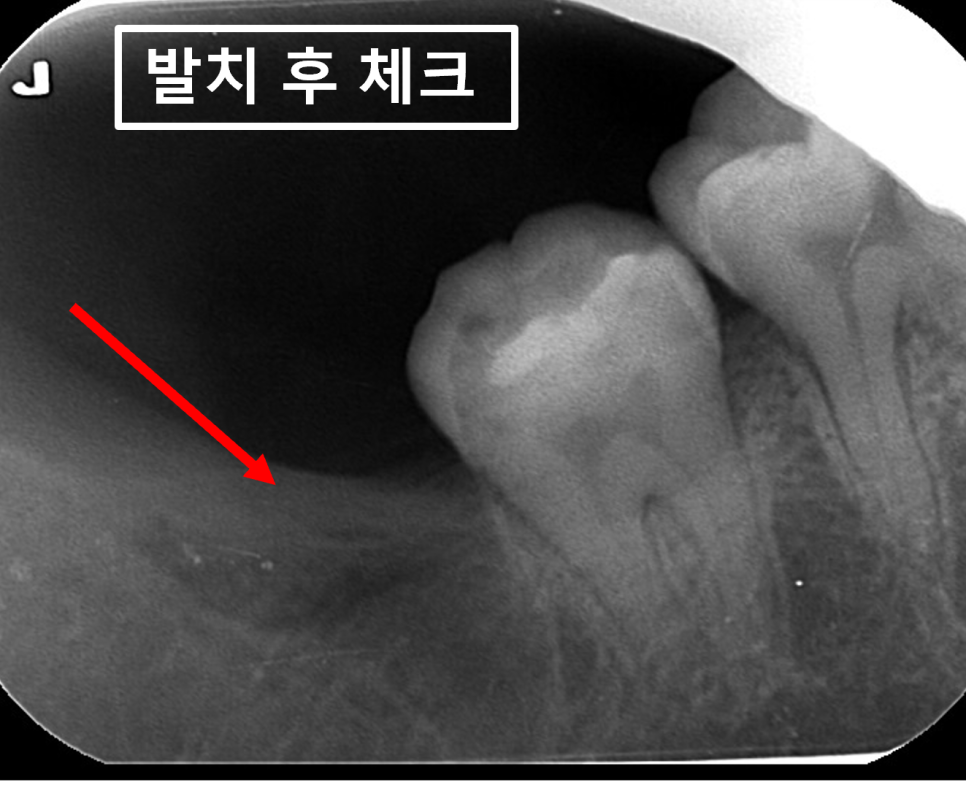

24.02.27(발치 후) – 26y 권OO님

임산부치과 매교역치과에서

임산부사랑니발치 후 촬영한 사진입니다.

소독, 봉합실 제거까지 잘 오셨고

정말 감사하다는 말씀을 해주셨네요.